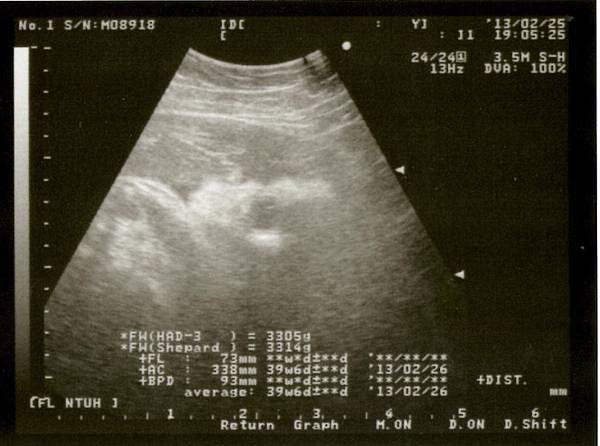

盼呀盼, 等呀等~都已經到了預產期3/4, 腹中的妹妹還是依然不發動~自從上周產假開始, 我為了要讓她自然產出, 硬是要求自己

每天要做青蛙蹲50下和走六層樓梯5回(因家裡是住六樓)~但到今天也是一樣沒消沒息

晚上還是照例進行第40周產檢(我從沒想到過, 會超過預產期才生). 產檢醫生一看到我, 就說"怎麼還沒生阿?"(因為小孩已足月且體重夠重)